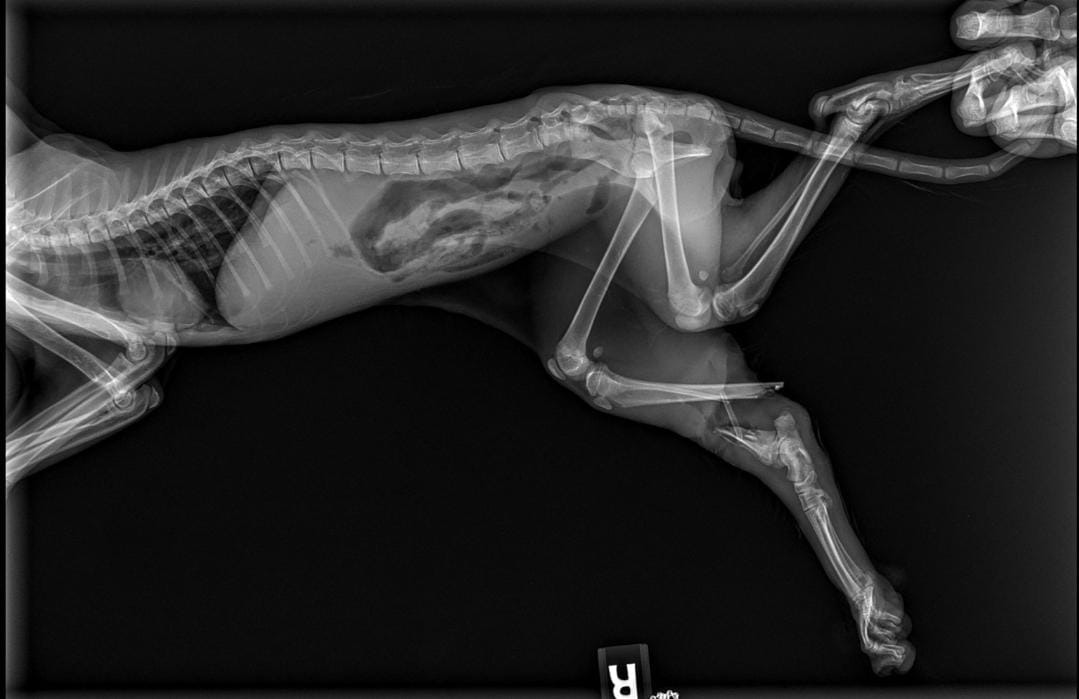

- URGENTE Hola mi nombre es Amanda Ruiz una persona desarmada dejo un gatito en Walmart dentro de un carrito y tiene fractura de cadera con hueso expuesto y no puedo dejar así ni cubrir los gastos.

- Urgent Hello, my name is Amanda Ruiz. An unarmed person left a kitten in a shopping cart at Walmart, and it has a fractured hip with exposed bone. I can't leave it like this or cover the expenses.

- Update se llevó al gatito a emervet 24/7 y el veterinario en turno nos explicó que para salvar al gatito hay que hacerle una amputación de su patita derecha el dinero que se está recaudando es para el pago de su operación y hospitalizacion también para medicinas y futuros tratamientos.

- The kitten was taken to Emervet 24/7 and the veterinarian on duty explained that to save the kitten, its right leg needs to be amputated. The money being raised is for the cost of its surgery and hospitalization, as well as for medicines and future treatments.